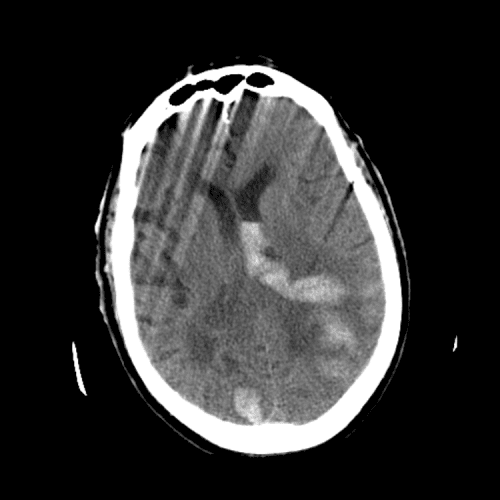

ACA and MCA territory infarct